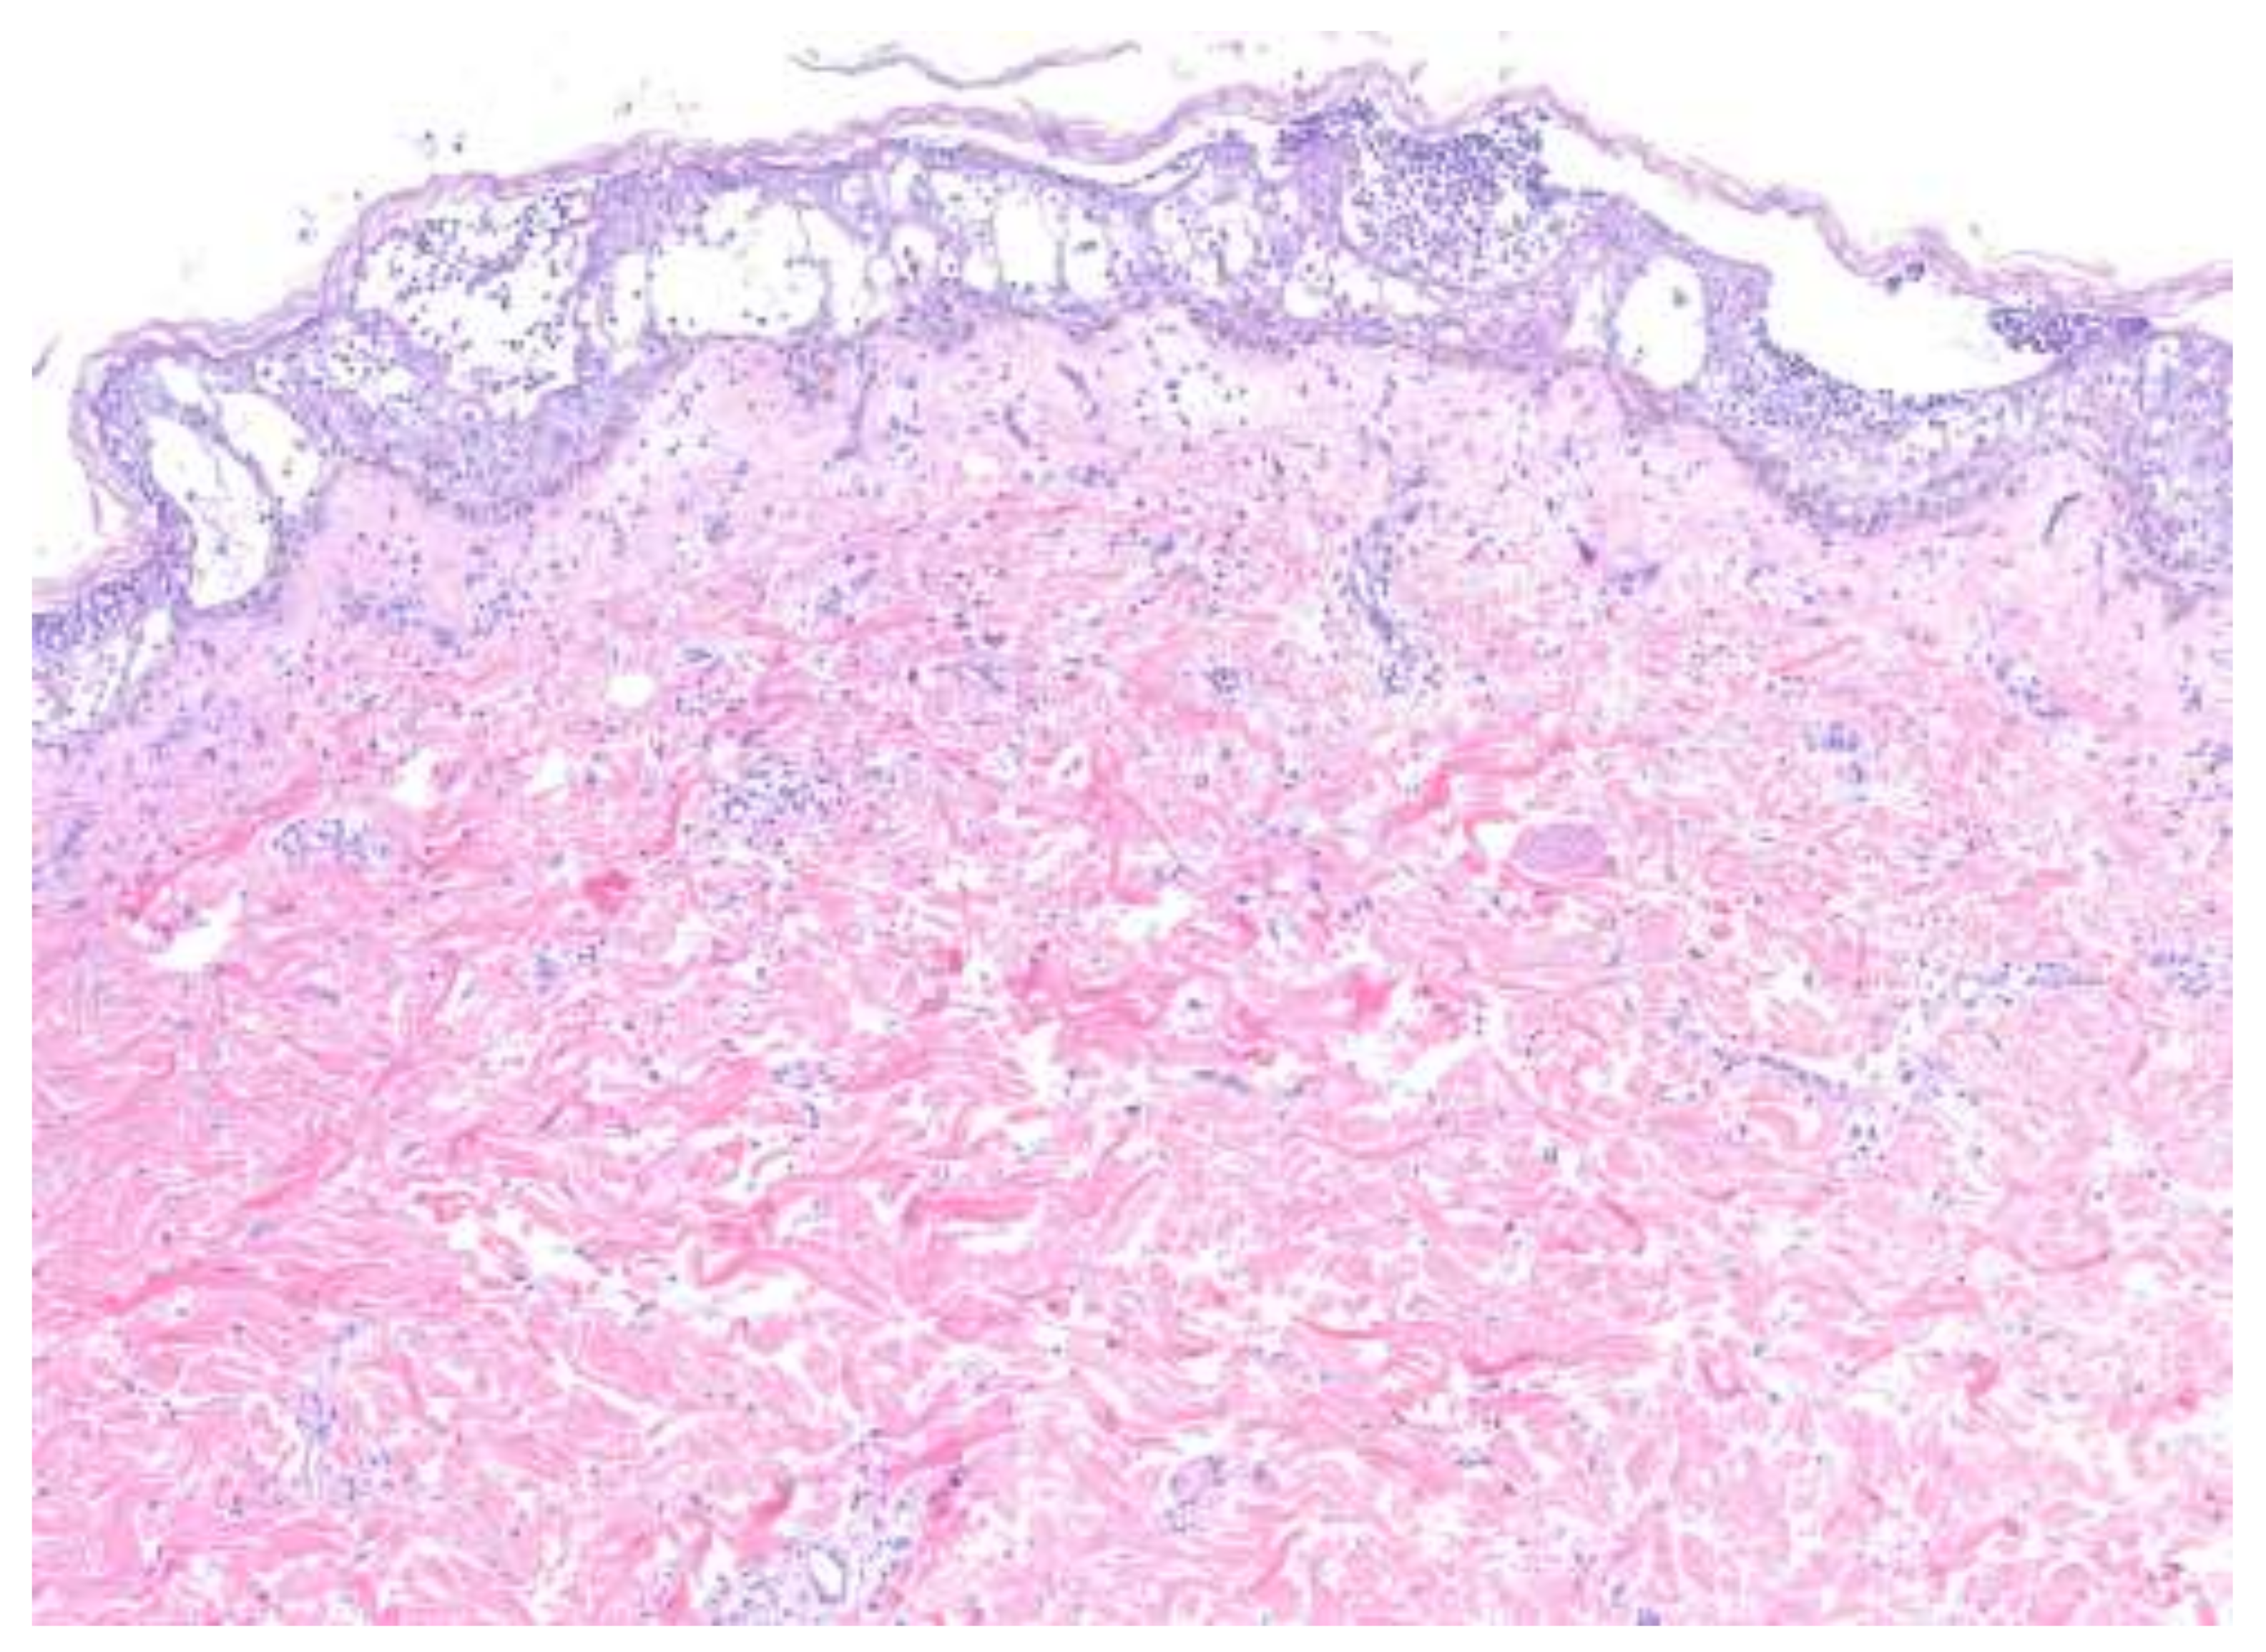

4. Histopathologic Features

| Generalized pustular psoriasis (GPP) | All PP subtypes contain sterile pustules [3]. Disseminated, painful erythematous lesions covered with aseptic pustules [3,8]. Severe systemic symptoms, including fever, malaise, fatigue, and arthritis, may be present [3,4]. | Fifth decade of life with slight female predominance [4]. | Pathogenesis: Disruption of the interleukin-36 pathway plays a major role (mutations in IL36RN), although there is significant heterogeneity in the gene pathways implicated [3,9,10]. The innate immune system, environmental factors, and genetic susceptibility all contribute [7]. Histopathology: Spongiform pustules of Kogoj in the epidermis and microabscesses of Munro [3,4]. Parakeratosis and psoriasiform hyperplasia [8]. | Topical corticosteroids, oral retinoids (i.e., acitretin), cyclosporine, methotrexate, TNF-α inhibitors (i.e., adalimumab), anti-IL-17 monoclonal antibody (i.e., secukinumab), anti-IL-23 monoclonal antibody (i.e., guselkumab), anti-IL-1β monoclonal antibodies (i.e., gevokizumab and canakinumab), IL-1R inhibitor (i.e., anakinra), PDE-4 inhibitor (i.e., apremilast) [3,4,7,9,11,12,13,14]. |

| Acute generalized exanthematous pustulosis | Sterile, pin-sized pustules overlying edematous and erythematous skin. Often appears on the face or intertriginous areas before spreading to the trunk and limbs [17]. Acutely accompanied by fever, neutrophilia, and eosinophilia [18]. | More common in adults with a slight female predominance [17]. | Pathogenesis: Drug-specific T-cell predominantly infiltrates with neutrophil accumulation mediated by IL-8 and GM-CSF [19,20,21]. Th17 cells are also involved in neutrophil activation [21]. Mutations in IL36RN found in some patients [20]. Histopathology: Spongiform subcorneal or intraepidermal pustules ± necrotic keratinocytes, vacuolar interface dermatitis, dermal eosinophilia, psoriasiform hyperplasia [17,22]. | Typically resolves within 2 weeks of discontinuation of the offending drug [20,23]. Topical steroids are often used for symptomatic relief [20]. Systemic corticosteroids or cyclosporine are useful in severe cases or with extracutaneous involvement [24,25]. |